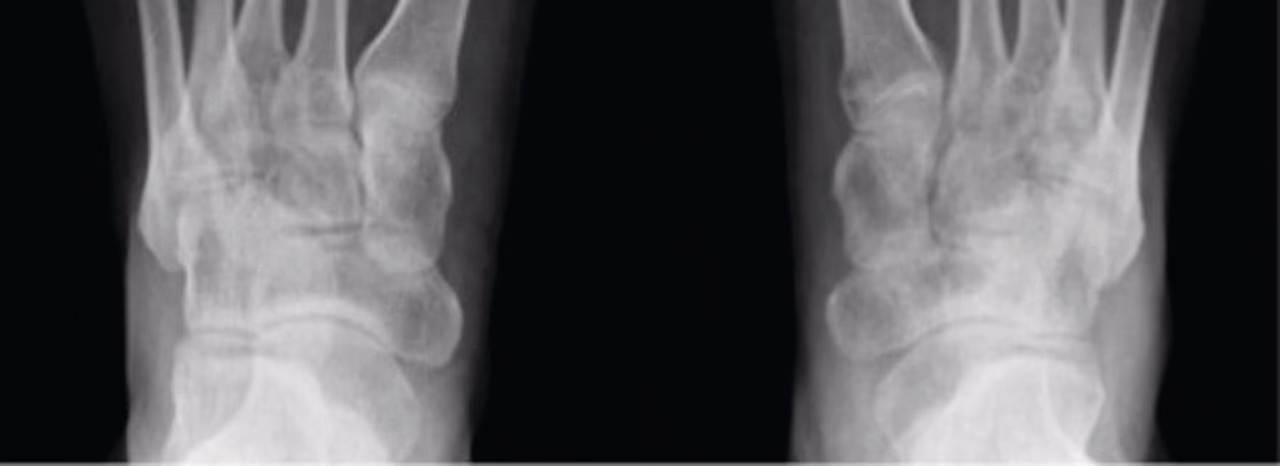

Radiologiske tegn ses typisk først 2-5 måneder efter sygdomsdebut. Den klassiske triade af radiologiske fund omfatter:

- Juxta-artikulær osteoporose (knogleskørhed nær leddet).

- Perifere knogleerosioner.

- Gradvis indsnævring af ledspalten.